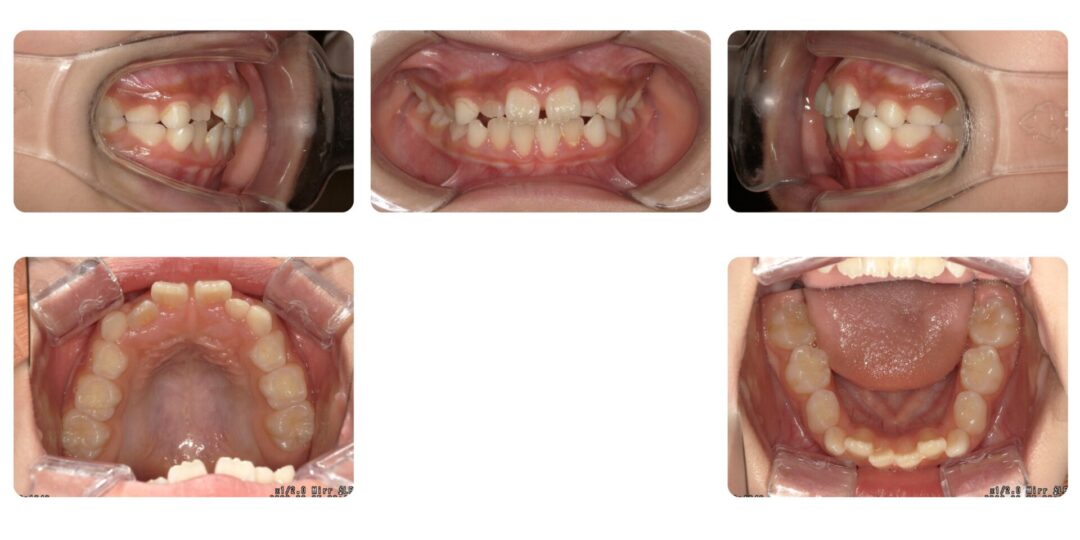

上下顎前歯叢生を伴うアングル二級咬合|初診時9歳

矯正治療前

治療内容

第一期治療 上下拡大床による歯列矯正

治療期間

1年8ヶ月

治療費用

自由診療 基本料金¥330,000 処置料¥3,300